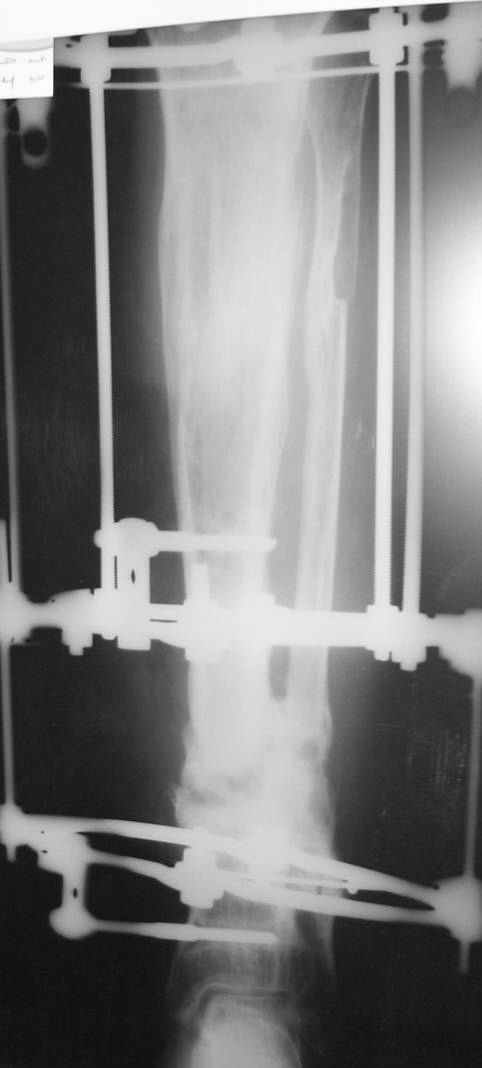

This Patient have to be treated by using Ilizarov bifocal bone transport, aproximatly as showen here.

from case archives - also see Ilizarov split fibula

"fibula pro tibia" transfer for segmental tibia defects